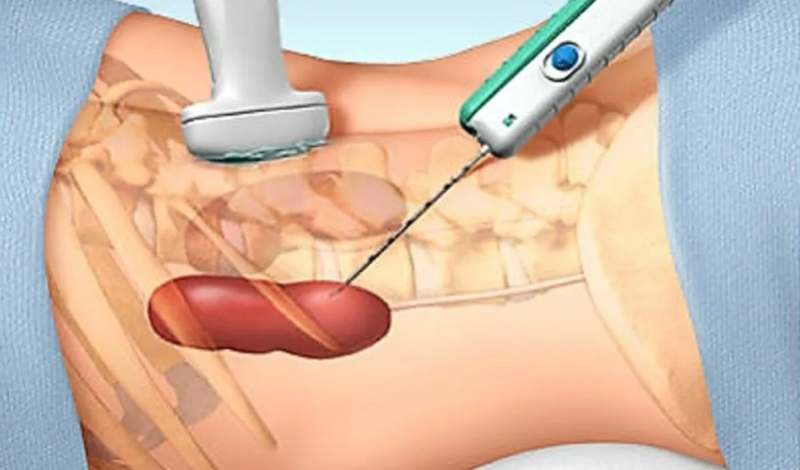

Simple & Complicated UTI

Urinary Tract Infection (UTI) is a common condition caused by bacterial infection of the urinary system,